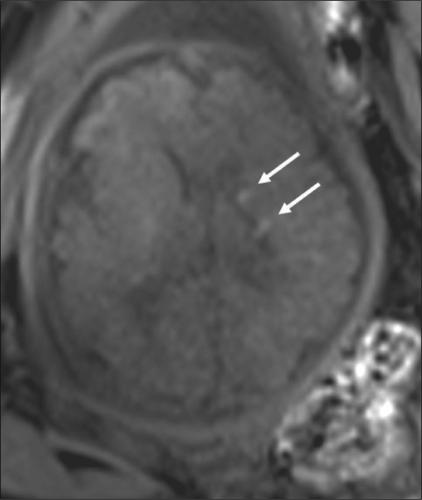

Pictorial essay: MRI of the fetal brain.

MRI is a useful supplement to USG for the assessment of fetal brain malformations. Superior soft tissue contrast and the ability to depict sulcation and myelination are the strengths of MRI. Subtle or inconclusive USG abnormalities can be confirmed or ruled out by MRI. In some cases, additional findings detected with MRI often help in arriving at a definitive diagnosis, which is necessary for parental counseling and for guiding management. Fast T2W sequences form the basis of fetal MRI. There have been no reports of deleterious effects of MRI on the fetus. A few case examples are presented to illustrate the advantages of MRI.